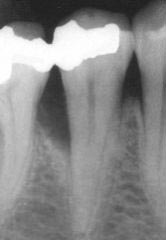

In werkelijkheid zijn de furcaties meestal niet zo duidelijk zichtbaar. Daarom is het moeilijk om in deze ruimtes tussen de wortels, de tandplak te verwijderen. Zelfs voor de tandarts of mondhygiënist is het moeilijk om alle tandplak en tandsteen uit de furcatie te verwijderen. Vaak is het beter om dit probleem op te lossen met behulp van chirurgie. Een moeilijk reinigbare furcatie zal een infectiehaard blijven en de prognose van een kies wordt slechter als de toegankelijkheid van de furcatie groter is. Kiezen in de onderkaak hebben twee wortels met een furcatie ingang aan de wang- en tongkant. Kiezen in de bovenkaak hebben drie wortels, waarbij de ruimte onder de wortels ook op drie plaatsen toegankelijk kan zijn. Onder zijn twee afbeeldingen te zien van een volledig toegankelijke furcatie van een kies in de onderkaak. Links op de röntgenfoto is te zien dat het bot tussen de wortels verdwenen is en rechts is hetzelfde tijdens de chirurgische behandeling met het 'blote' oog te zien.

Naast deze 'klinische' gegevens is het belangrijk om ook röntgenfoto's van de tanden en kiezen te hebben. Op deze foto's is het verloop van het botniveau tussen de tanden en kiezen te beoordelen, maar kunnen ook andere problemen, welke van belang zijn voor de behandeling, opgespoord worden.

Boven zijn twee röntgenfoto's te zien, op de linker is een normaal botniveau zichtbaar, terwijl op de rechter foto, het botniveau sterk verlaagd is door parodontale afbraak.